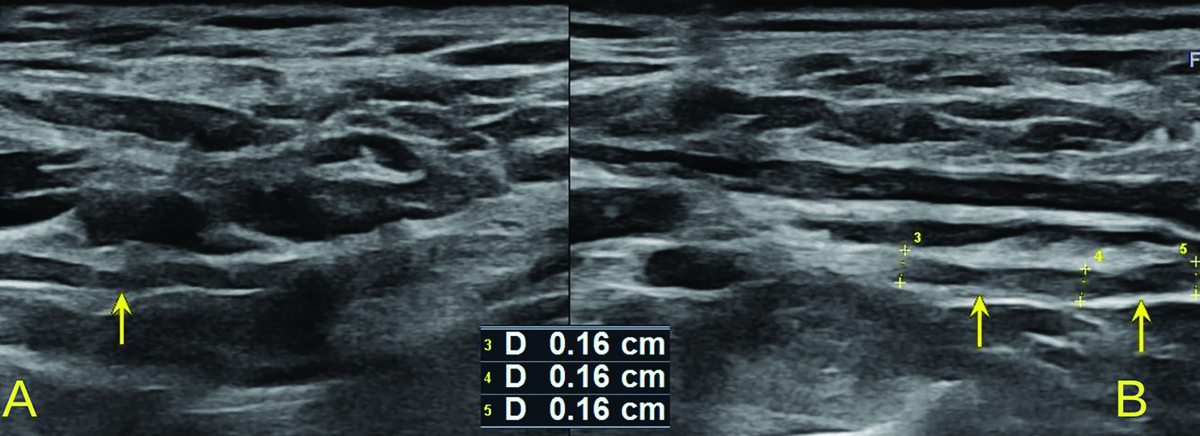

Figure 2

High-resolution ultrasound image of LTN torsion with an ”hourglass-like” constriction sign – marked with arrow (A) with comparison to the asymptomatic side (B) in 50-year-old patient with Parsonage-Turner syndrome. Images obtained by author with a 3-19 H linear probe of the Alpinion XCube90